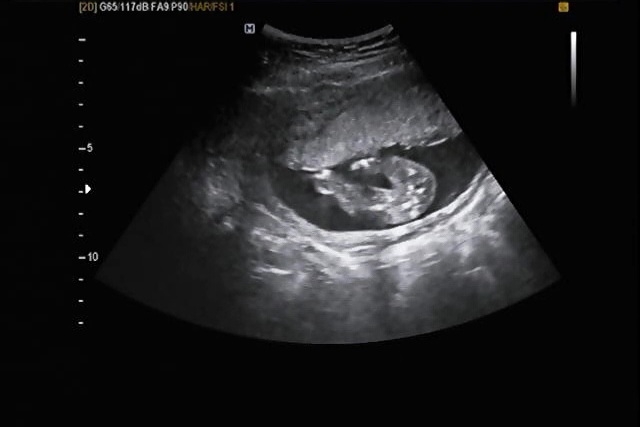

16주 아기 성별 확인하고 왔어요.

한달을 꼬박 기다려서 드디어 16주 검진하고 왔어요. 2주간격은 기다릴만한데 한달은 은근 힘드네요😂 선생님께서 성별 보여주신다고 이리저리 움직여가면서 확인해주셨는데 아기가 한쪽 다리를 계속 접으면서 안 펴더라구요. 일단은 사이에 보이는게 없어서 딸일 것 같다는 뉘앙스를 주셨는데 더 확실한건 19주검진 때 다시 확인해봐야 할 것 같아요. 사실 저는 성별은 바라는거 없고 아기 심장 잘 뛰는거랑 기형아 검사가 제 최대관심사라 2차기형아검사 결과랑 20주 정밀초음파에 온 신경이 곤두서있어요. 안타까운 이별영상들을 몇번 봤더니 출산까지 맘놓고 있기가 참 어렵네요ㅠ,ㅠ 찰떡아❤️ 아프고 힘든 거 엄마가 다 할테니까 우리 찰떡이는 아프지말고 건강하게 엄마 품에 폭 안겨줘🫶